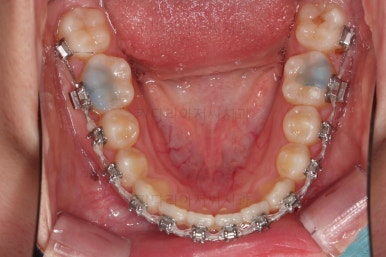

장치를 처음 부착한 사진입니다.

이번 환자분은 특징적으로 윗니의 장치와 아랫니의 장치가 다르죠.

윗니는 좀 더 심미적인 세라믹으로 선택하셨고 아랫니는 비교적 저렴하고 부피가 약간 작고 튼튼한 메탈로 진행했습니다.

비교적 조기에 앞니는 가지런해졌고요.

대신 교합이나 기울어진 느낌 등 디테일을 맞추기 위한 작업을 추후에 계속 하게 됩니다.